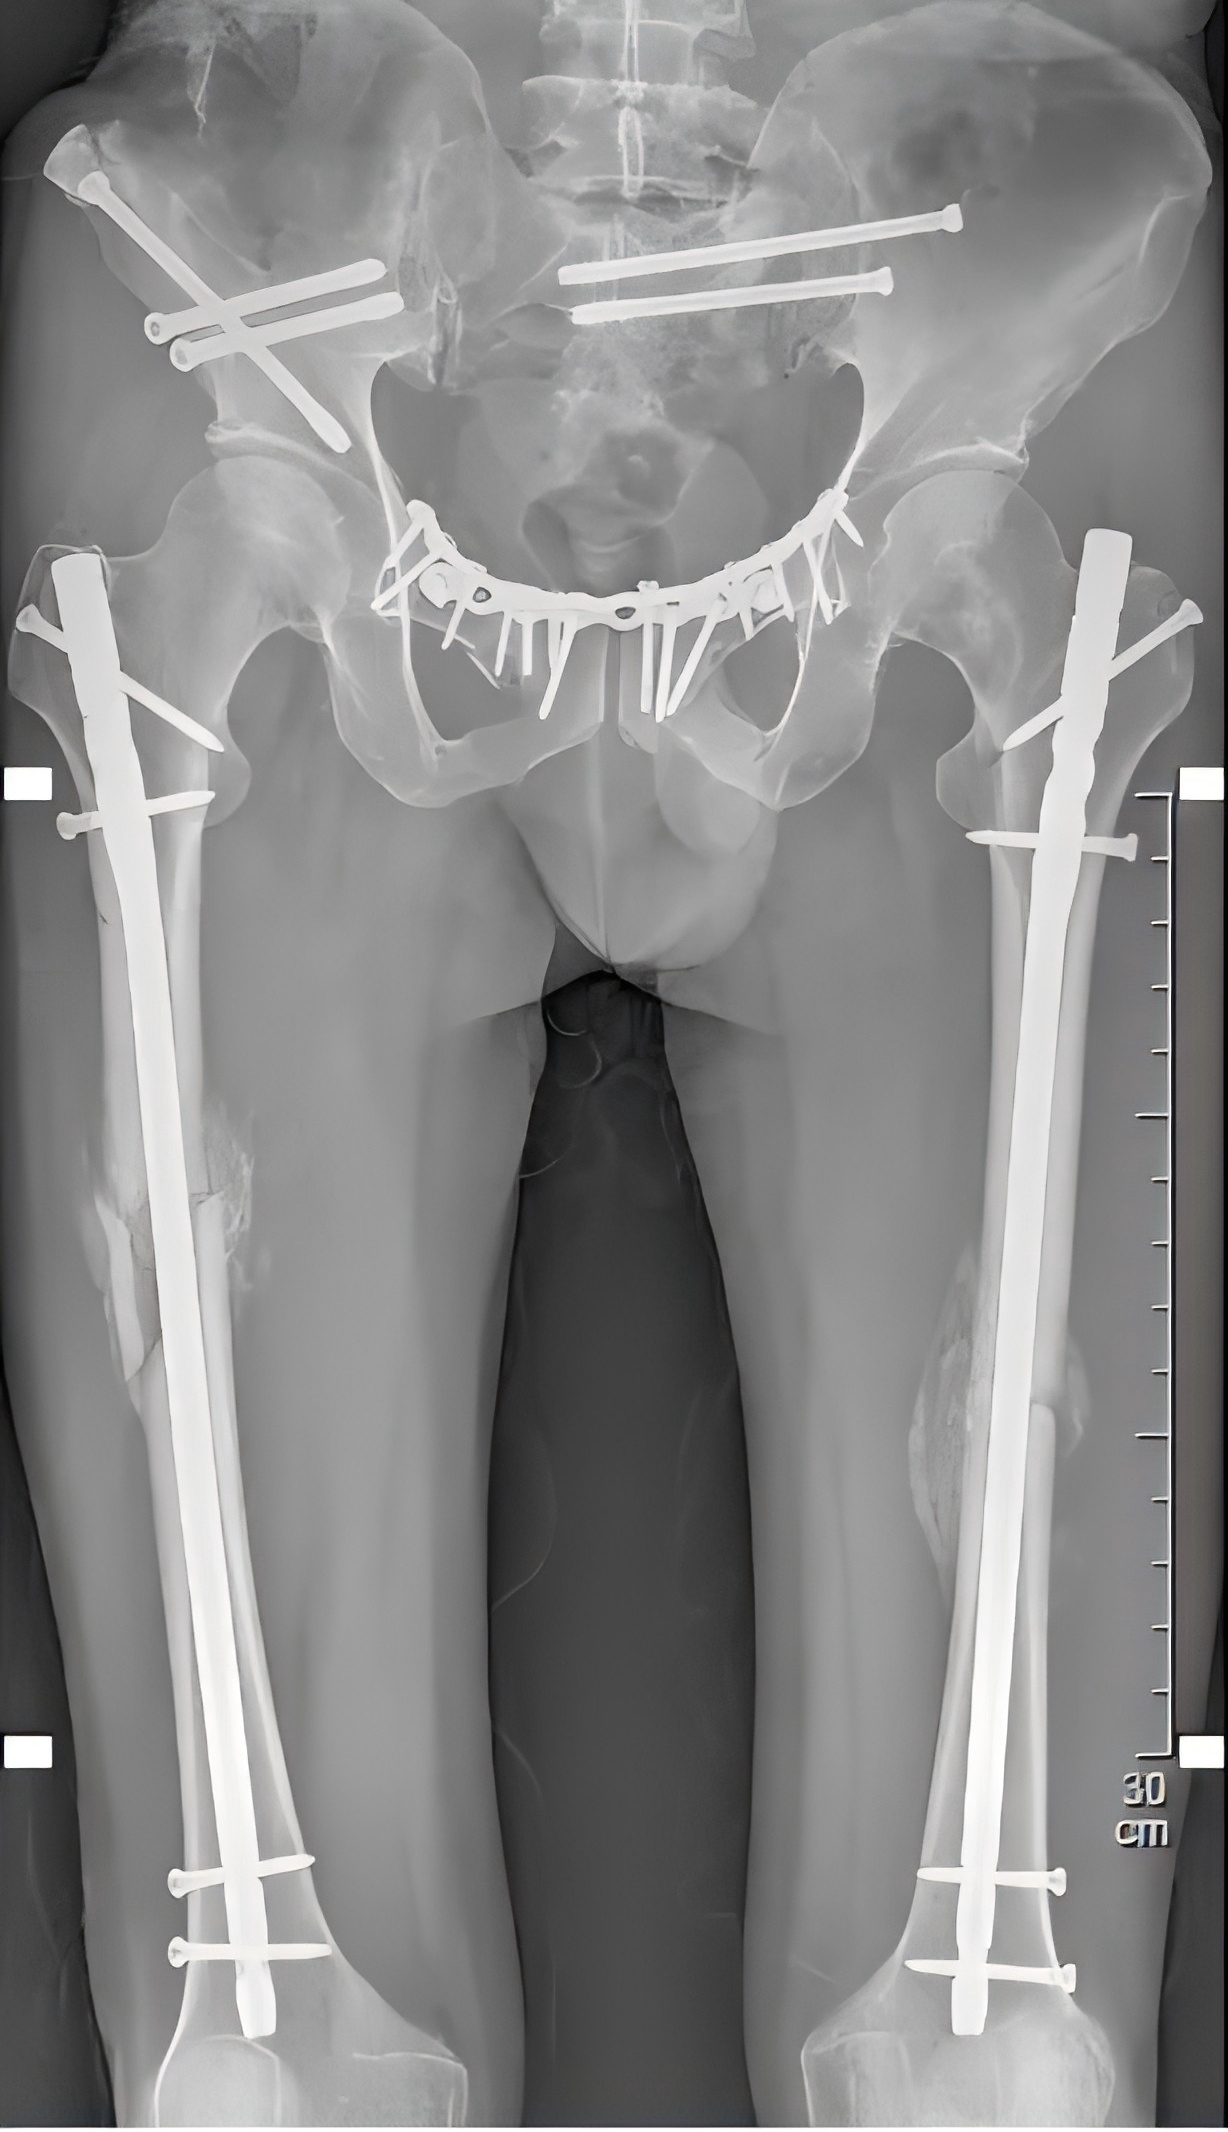

殷小軍團隊基于損傷控制理念,為患者量身定制了微創手術方案。手術分為兩期進行:待患者生命體征穩定后,一期先行骨盆及一側股骨骨折微創內固定治療;二期行另一側股骨骨折微創內固定手術。

醫療團隊僅用了11天,便為患者完成了多發骨折的手術治療。手術后一周,患者即可進行半臥、翻身活動,既減輕了護理難度,也增強了患者戰勝疾病的信心。

(患者術后X片)

術后1個月,復查顯示患者的骨折處愈合情況良好,大量骨痂形成。

術后40多天,患者已能下床活動,平穩地行走了。